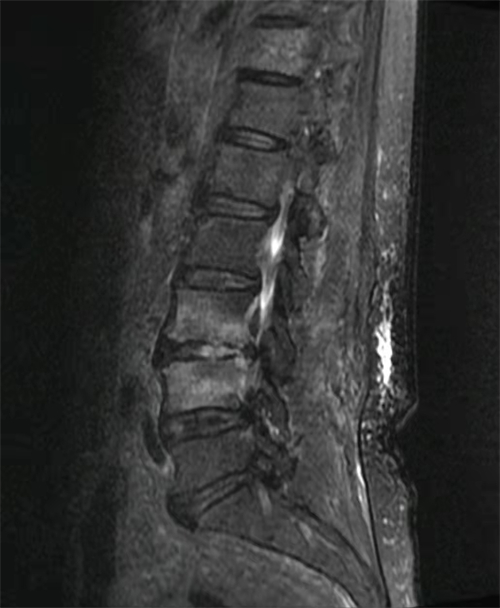

第一步,“活下去”,把感染彻底控制住。在仔细研究患者的影像学资料并得到手术室的配合后,杜建伟团队决定立即为患者实施微创脊柱内镜技术,清除腰椎感染病灶,并将双腔管置入感染的腰椎间隙内,细管给予敏感抗生素,粗管引流,成功做到感染病灶精准靶向给药,同时配合静脉滴注敏感抗生素,全身与局部协同治疗。术后第二天,患者的腰痛症状就明显缓解,血液炎症指标也有明显下降,并随着时间推移,指标逐步恢复正常。

杜建伟介绍,由于人口老龄化、患者合并疾病增多、侵入性治疗及外科手术的增加等原因,腰椎感染的发病率逐年提升,中老年患者比例逐步增加。近年来,脊柱内镜微创手术不断发展,目前已成熟应用于治疗腰椎间盘突出症、腰椎管狭窄症等腰椎退行性疾病,并取得满意的疗效。对于腰椎感染,同样适用。如此病例中的手术,是在局麻下进行的,减少了全身麻醉的风险。手术中,只要在腰部开一个1厘米长的切口,不破坏腰背肌,内镜可直达椎间隙,顺利清除病灶,置入的双腔管可同时进行灌洗与引流,精准靶向给药,疗效迅速且确切,非常适用于体弱多病、合并症较多的老年患者。